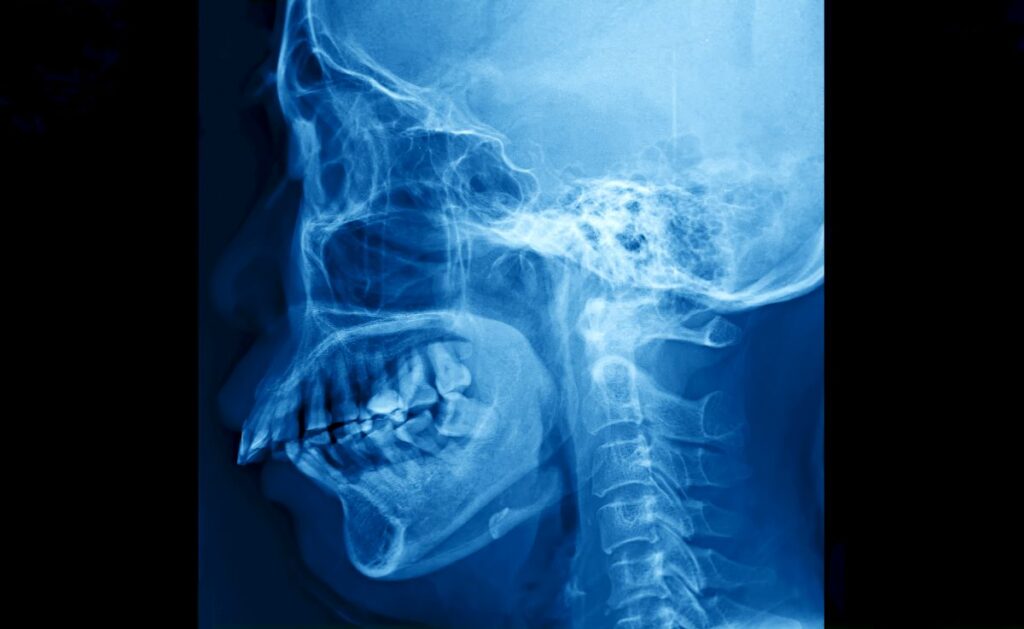

How Mouth Breathing Affects Facial Growth in Children

Signs Your Child’s Jaw May Not Be Developing Properly